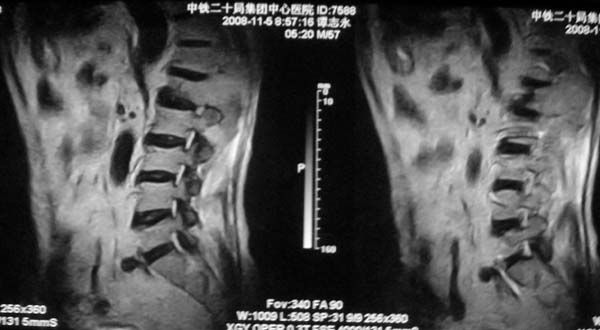

病史特点:

1.中年男性

2.腰疼,双下肢麻木1月。

3.ct 可右肾上腺占位,腰1椎体及附件可见骨质破坏及软组织肿块。

4.mri:腰1椎体及附件t1wi低信号,t2wi高信号。

考虑右侧肾上腺癌骨转移.或右肾上腺及骨均为转移瘤。